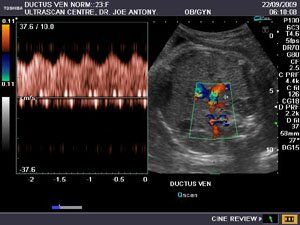

4D image of 29 weeks pregnancy, multiple anomalies: Clinch hand, omphalocoele, single atrium